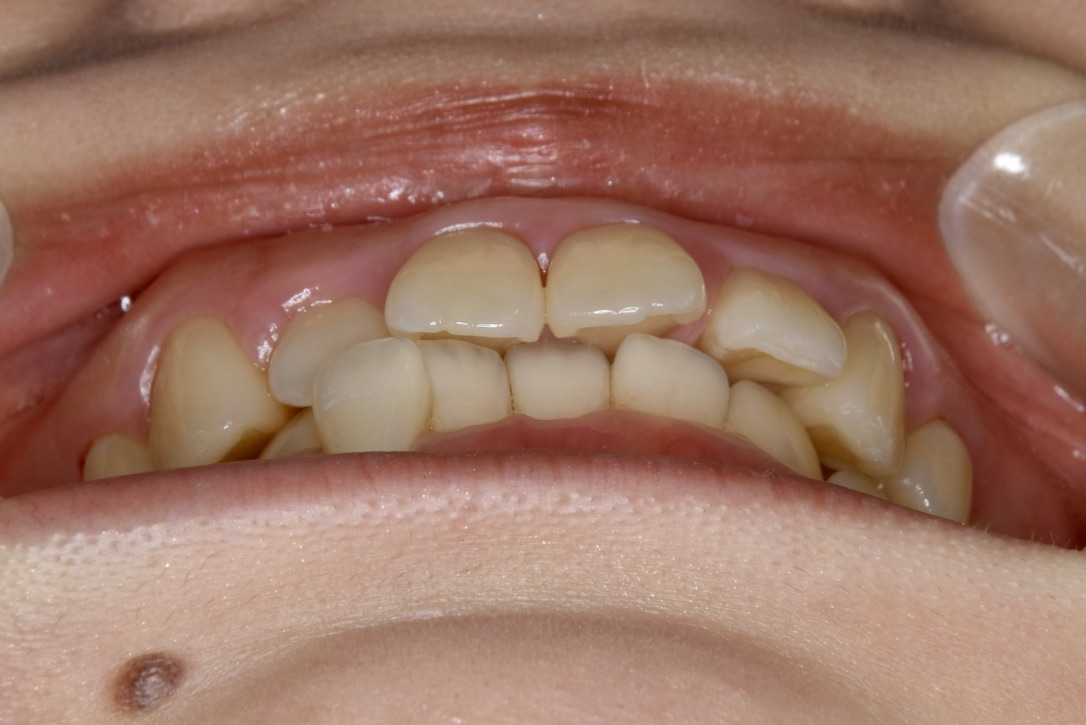

21歳 女性 治療期間:1年1ヶ月

叢生(ガタガタ)

マウスピース矯正装置(インビザライン)

BEFORE

AFTER

診断名・主な症状

叢生

治療内容

上下とも歯並びの横幅を広げながら、でこぼこを解消しました。

マウスピース矯正(インビザライン)

抜歯あり(智歯抜歯)

1年1ヶ月

10回

85万円程度(税別)

リスク・副作用

痛み、歯肉退縮、歯根吸収、抜歯に伴う出血や腫れが生じることがあります。